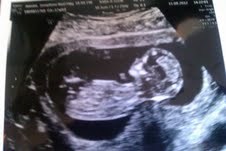

Min kærste og jeg fik set vores lille bølle for første gang - inkl. fire fingre på hver hånd og et bankende hjerte med fire hjertekamre! var virkelig overrasket over, hvor meget man kan se..

det var en meget livlig lille bebs, der ikke rigtig ville ligge som den skulle. Til sidst lykkedes det alligevel jordmoderen at få målt nakkefolden, og vi er så heldige, at risikoen for downs er lav!

Jeg fik hele tre billeder med hjem og I skal da ikke snydes for mit yndlings